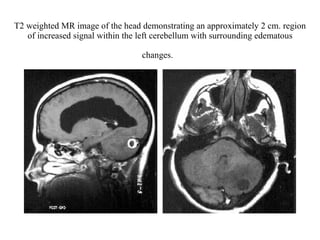

von Hippel-Lindau disease HBs of the CNS Figure 1 MRI scan of two small solid cerebellar HBs (arrows) in a 52-year-old VHL patient. Figure 2  MRI scan of a typical cystic cerebellar HB in a 39-year-old non-VHL patient. Figure 3 Two solid brain stem HBs and a cystic HB in the cervical spine in a 32-year-old VHL patient. Figure 4  An HB in cervical spine in a 21-year-old VHL patient: MRI with contrast (a), superselective angiography before (b) and after (c) preoperative embolization. Figure 5 Two small spinal HBs in the thoracic region (a and b) in the same patient as in Figure 4, three years later. Figure 6 A large solid recurrent HB 11 years after the primary total removal in a 66-year-old non-VHL patient.